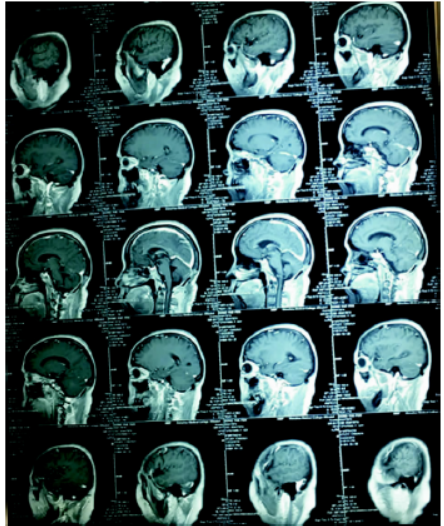

患者董某某,女性,53岁,言语不清40余天。既往有高血压,糖尿病,精神分裂症病史。查体:神志清楚,对答切题,言语含糊,闭目难立、轮替试验等均正常,四肢肌力、肌张力正常,双侧病理征阴性。血常规、肝肾功能、电解质均正常。胸部CT未见明显异常。头颅MRI提示:右侧小脑上部短T1,长T2信号肿块影,边界不清晰,周边可见水肿带,肿瘤大小约2×2×1.5 cm。肿瘤增强后呈不均匀环形强化(图1、2)。入院诊断:右侧小脑肿瘤。

图1 MRI平扫T1呈低信号,T2呈高信号,FLAIR呈稍高信号,增强呈不均匀强化。